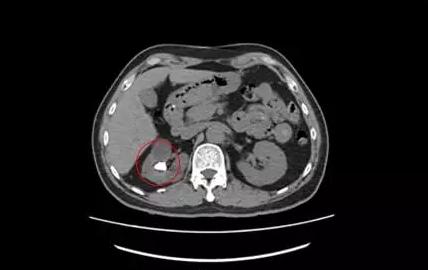

术前CT

在B超的监视引导下,于右侧腰背部11肋间用PTCD针穿刺右肾含石上盏,拔除针芯后可见尿液流出,然后逐步扩张经皮肾通道并置入工作鞘,然后置入超细经皮肾镜,经输尿管镜可看到,结石大小约1.6X1.2X1.0CM,黄褐色,质地硬,表面粗糙。